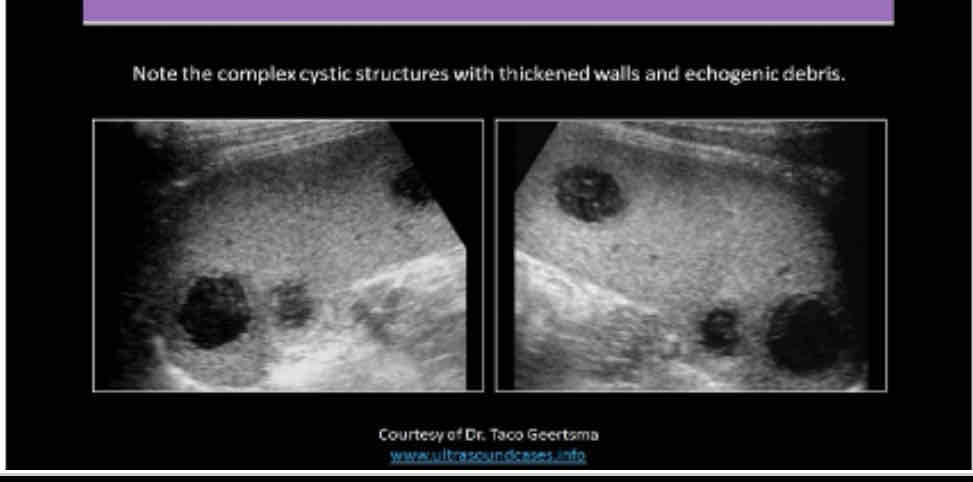

What does the following describe?

•It is rare. May be associated with endocarditis, septicemia and trauma

•May see them status post splenectomy

•Symptoms include pain, dizziness, faintness,

•Lab Testing: decreased hematocrit, fever, increased WBC and possible septicemia

splenic abscess

What does the following describe?

•Sonographically: Complex fluid collection with internal echoes

•Irregular borders

•May see septations and pleural effusion

•Dirty shadowing from gas producing organisms

splenic abscess